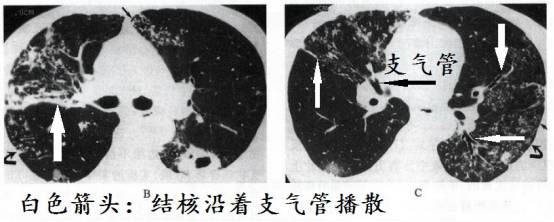

结核容易沿着支气管播散

结核的特点之一便是沿着支气管播散,在支气管周围形成密密麻麻的小结节,在外周小支气管播散形成树芽征。虽然其他疾病也会这样,但是结核相对更常见。

所谓结核沿着支气管播散,简单的说就是病灶大部分都分布在支气管周围。